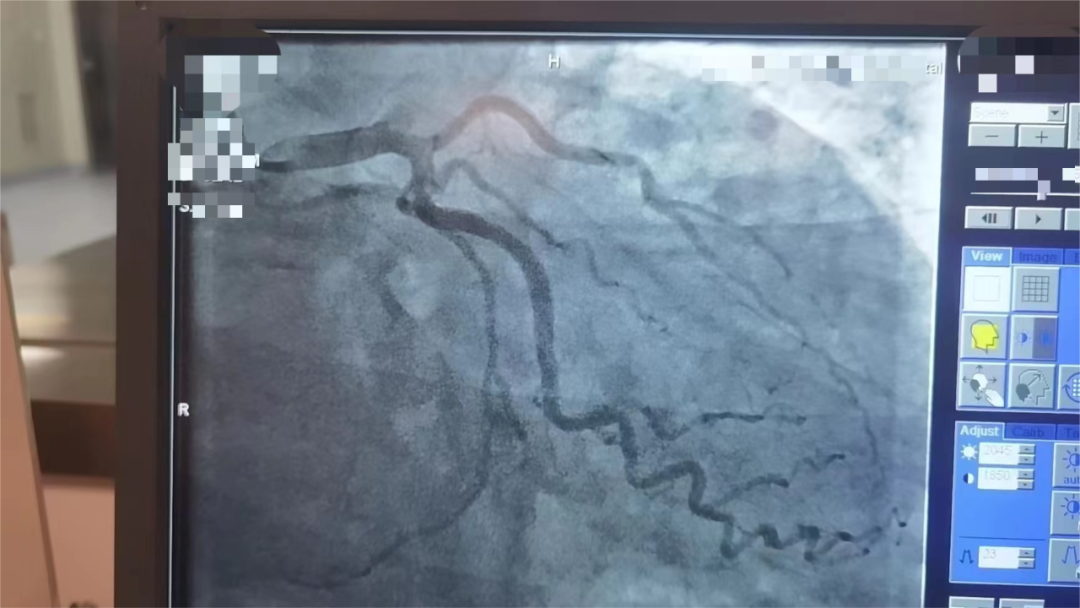

医院一查竟是急性心梗!为他行紧急冠脉介入手术,抽出血栓,顺利置入2枚支架,开通完全堵塞的心脏前降支血管。